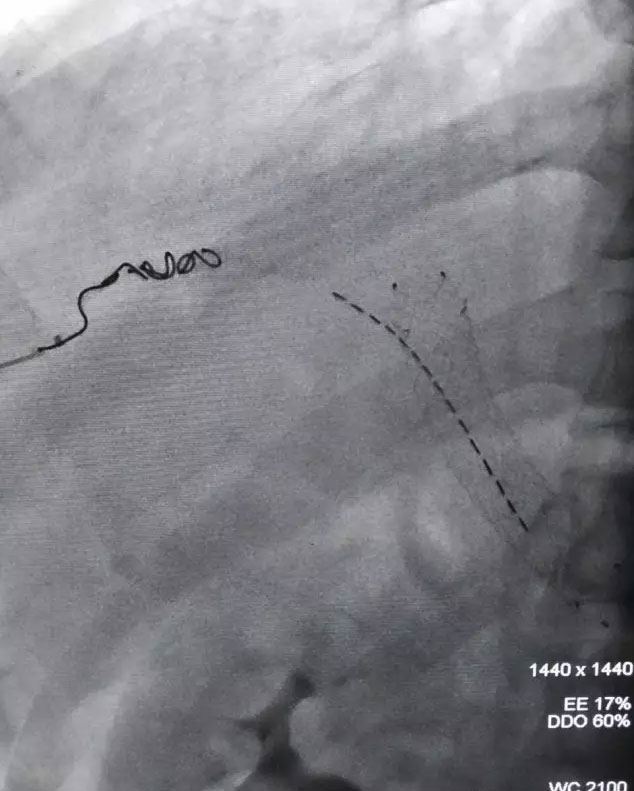

今年初,介入中心医务工作人员经历十二小时的手术,成功的为五名肝癌患者实施了“门静脉近距离放疗支架植入”治疗,这次手术首次运用“采用双导丝技术门静脉粒子支架植入”治疗,标志着过去患者到上海才能完成的手术,如今在家门口也可完成。

这里值得一提的是——双导丝操作技术,即在肝脏上一个穿刺针眼里,进入两根导丝,一根导丝控制支架,达到开通血管作用,另一根导丝控制放射性粒子条位置,粒子条起到内照射肿瘤作用,但需要掌握的操作技巧精髓部分是非常困难的。